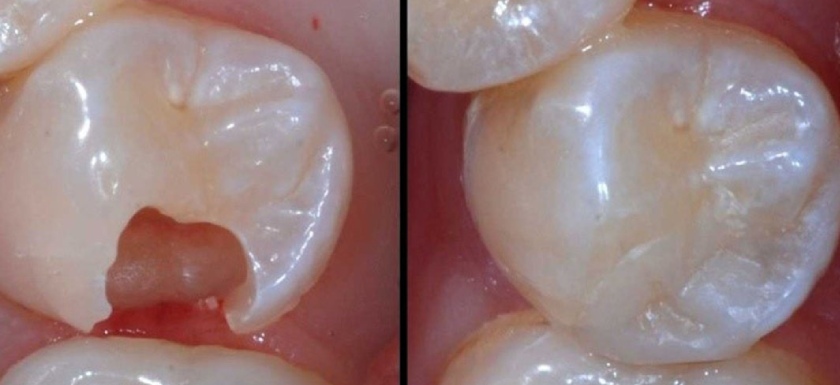

Trám răng thẩm mỹ

Đây là kỹ thuật tương đối đơn giản trong nha khoa. Bác sĩ sẽ sử dụng vật liệu trám chuyên dụng (thường là composite) để trám kín phần răng bị khuyết, bảo vệ các mô răng khỏi sự tấn công của vi khuẩn gây hại và tái tạo hình dáng ban đầu của răng.

Phương pháp này thường được áp dụng cho những trường hợp răng hàm bị vỡ nhẹ, phần răng bị mất không quá lớn. Còn đối với những trường hợp răng bị vỡ lớn thì nên bọc răng sứ, bởi nếu sử dụng miếng trám trong trường hợp này sẽ rất dễ bị bong tróc, không đảm bảo độ bền lâu dài.

Trám răng hàm bị vỡ